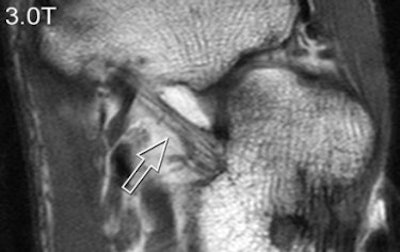

| A 31-year-old healthy male volunteer. Axial T1-weighted fast spin-echo images of foot show superior delineation of spring ligament (arrow) at 3 T (top and middle) as opposed to 1.5 T (below); 3.0TGR = 3.0T with GRAPPA algorithm. No significant difference was found between (top) and parallel (middle) acquisitions at 3 T; visualization of this ligament was rated very good at 3 T and as moderate at 1.5 T (below) by both radiologists. |

According to the results, GRAPPA MR resulted in a 44% reduction in scan time compared with conventional imaging. SNRs and CNRs doubled on the SPGR sequence at 3 tesla. These 3-tesla images also demonstrated comparable edge sharpness.

Image quality was rated highest on 3-tesla images. The axial T1-weighted sequence was given an average score of 3.4 at 3 tesla for parallel and normal acquisitions versus a score of 2.8 for 1.5 tesla. Visualization of ligaments and tendon abnormalities were also rated highly on parallel 3-tesla MR.